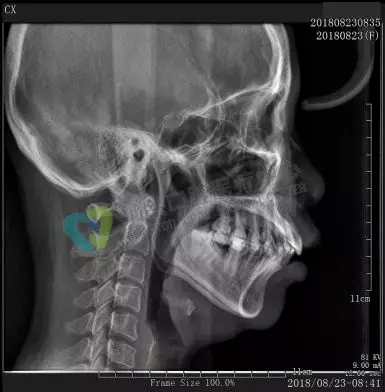

口腔CBCT,可對(duì)牙齒、頜骨進(jìn)行計(jì)算機(jī)斷層掃描,重建三維圖像,可多角度再現(xiàn)牙齒、頜骨內(nèi)部結(jié)構(gòu),各個(gè)組織間的關(guān)系。圖像非常清晰,具有很高的密度分辨力。